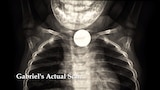

Parásitos asesinos

: Una batalla de vida y muerte entre la medicina moderna y la evolución mientras los pacientes luchan contra los parásitos.